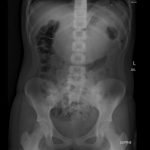

In the abdominal radiograph, a nonspecific and non-obstructive bowel gas pattern with no air-fluid level was noted, however the stomach was distended with soft tissue. The CT abdomen/pelvis revealed a distended stomach with undigested heterogeneous contents (presumed bezoar).